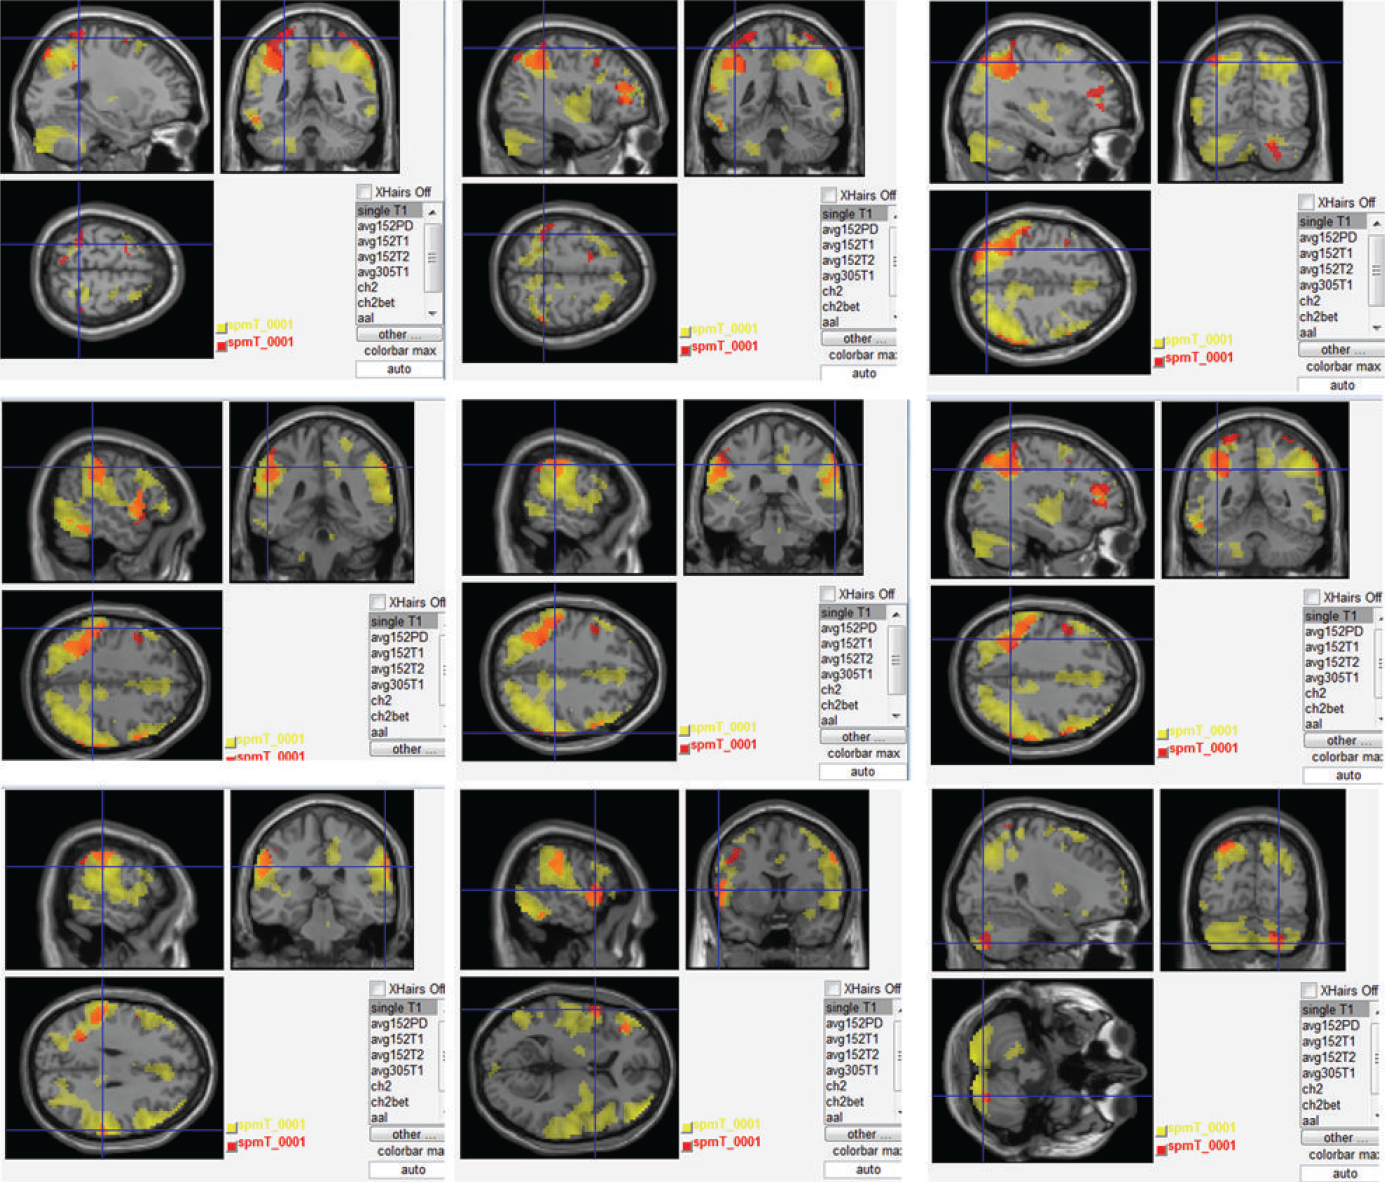

acupuncture:points:points des meridiens:gros intestin:kong-001-irmf.png

kong-001-irmf.png